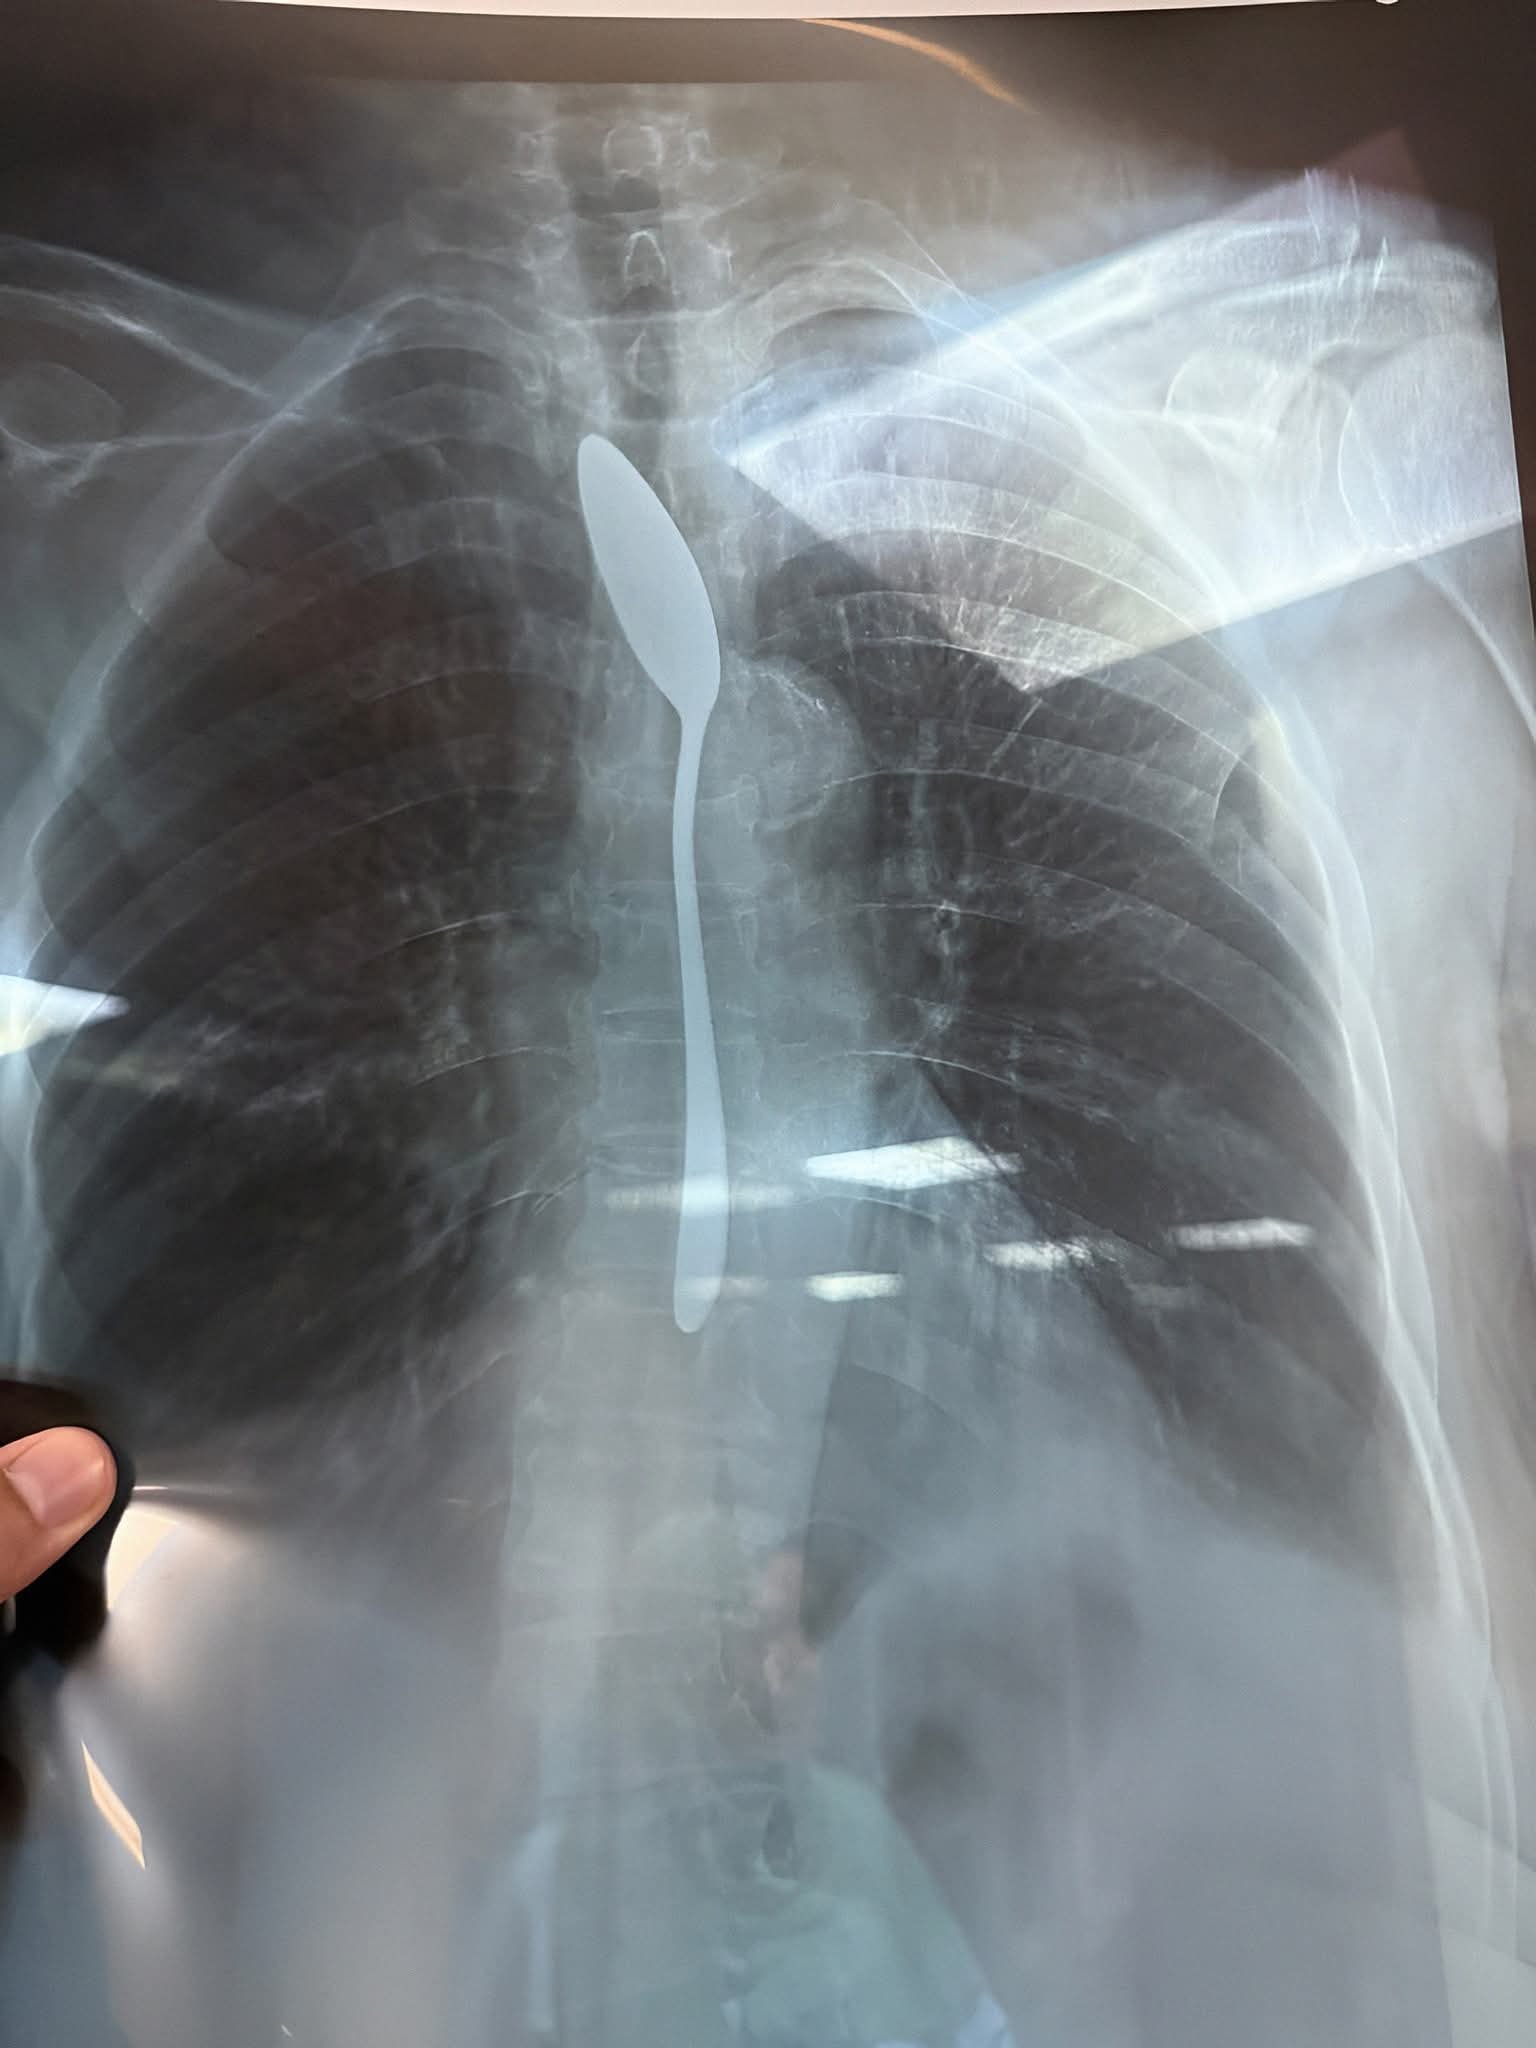

وبعمل الآشعه اللازمه أظهرت صورة واضحة لملعقة شاي كاملة مستقرة داخل المريء، مما استدعى تدخلا عاجلًا لإنقاذ حياتها.